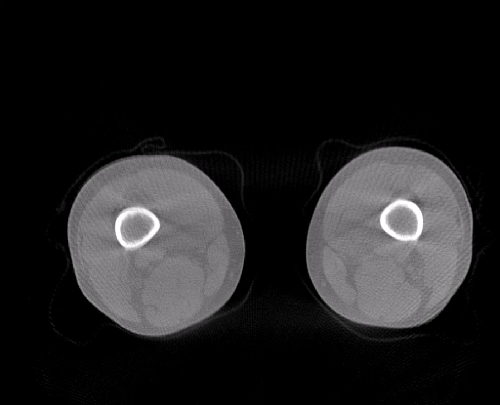

对于WR-3D技术的问世,主要解决了两大核心问题:1、解决了普放DR漏诊率高的现状,常规DR设备仅有某一角度的二维影像、密度信息极差,而WR-3D能获得更丰富的诊断信息,多角度拍摄三维重建影像,任意角度任意切面以及高敏感的密度信息;2、解决了CT无法获得立位(负重位)的三维影像,WR-3D无论是在断层图像重建、MPR多平面重建、VR体绘制都有着优异的表现,而对于临床诊断尤其是骨科,负重位的影像更具有临床价值。患者在负重位状态下肌肉状态、关节间隙及骨骼力线等都与患者平躺时是明显不同的。因此WR-3D在术前精准规划与术后精准评估方面有其非常重要的临床价值。

负重位状态下WR-3D断层重建图像